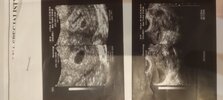

Hej dziewczyny w którym tygodniu dowiedziałyście się, że to ciąża bliźniacza?

Pokażcie swoje zdj z 6tc.

Ja byłam wczoraj 5+6 i mam takie zdj. Oczywiście lekarz powiedział że jest ok ale nie daje mi spokoju że są tam 3 kropki... Czy to możliwe że to bliźnięta? [emoji16]